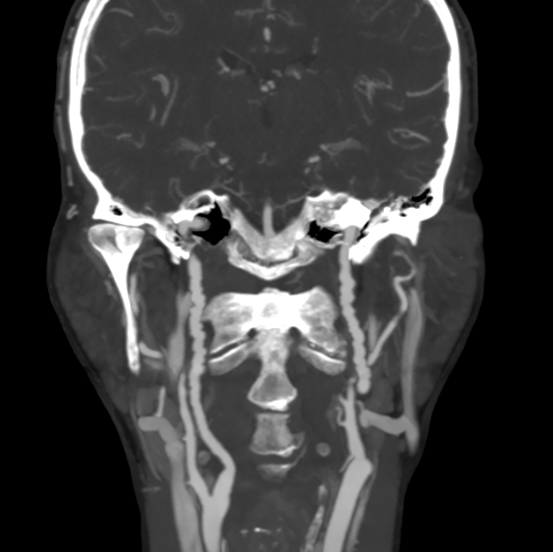

Бусы, о которых поговорим мы, найдены в шее одной из прекрасных пациенток, посетивших меня на КТ.